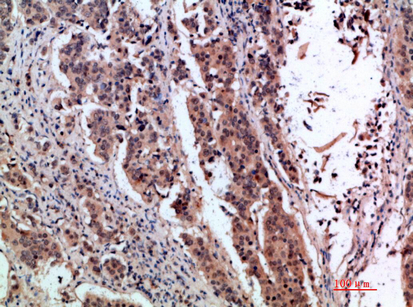

IHC-P,IF-P,IF-F,ICC/IF,ELISA

IHC-P 1:50-200, ELISA 1:10000-20000, IF-P/IF-F/ICC/IF 1:50-200